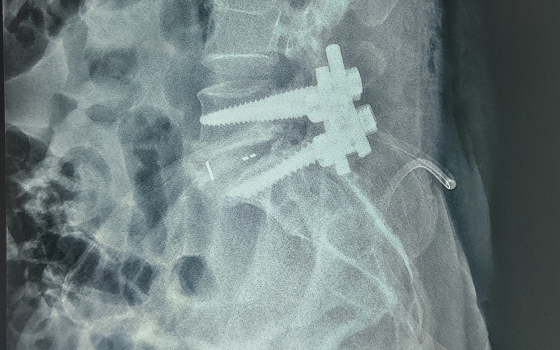

Dr. Somashekar D is an experienced spine surgeon in Bangalore. He is currently practising as a Consultant - Spine Surgery at Manipal Hospital Jayanagar, Bangalore. With nearly 10+ years of expertise in spine care, Dr. Somashekar has established himself as a highly skilled spine surgeon, contributing to over 1,500+ spine surgeries independently, ranging from simple decompressions to complex spinal reconstructions. His practice is deeply rooted in precision-based techniques and evidence-guided clinical protocols, ensuring both safety and long-term functional outcomes for his patients. He is a top spine surgeon in Jayanagar.

We offer comprehensive treatment for spine issues that is on par with any leading spine center worldwide. Our services encompass both non-surgical and surgical treatments tailored to address your specific condition. Our expertise covers a wide range of spine surgeries, including minimally invasive spine surgery, cervical spine surgery, scoliosis surgery, and complex spine surgeries.

Covers a wide range of spine surgeries, including complex spine surgeries.